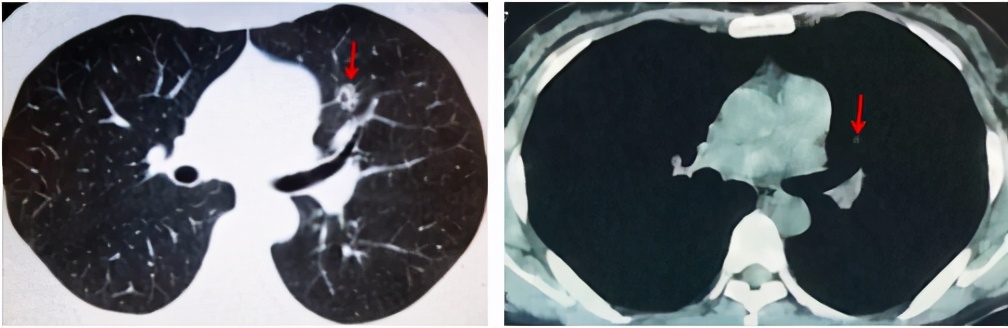

放射科大夫认为肺内结节恶性可能性大,并分析了肺内原发癌与转移癌在CT影像学表现上的差异。肺内原发癌目前以腺癌最为常见,可有各种密度,包括磨玻璃样改变、部分实性或实性,常有分叶、毛刺和血管集束征,可有空泡征或细支气管充气征,也可因为血供不足、坏死形成空洞。肺单发转移瘤以实性转移多见,偶可有磨玻璃结节,以下肺多见,边界光整,可有分叶,密度多均匀,转移瘤形成空洞的几率低。

本例患者胸部CT提示左肺上叶结节影,内见空洞形成,邻近气管走行迂曲,壁薄光滑,病变边缘可见毛刺,从CT影像学(图2)考虑肺原发癌可能性大,但有时原发癌和转移癌不好区分,最终还需要病理证实。

图2 .肺部CT示左肺上叶结节(箭头所示) 图2 肺部CT示左肺上叶结节(箭头所示)